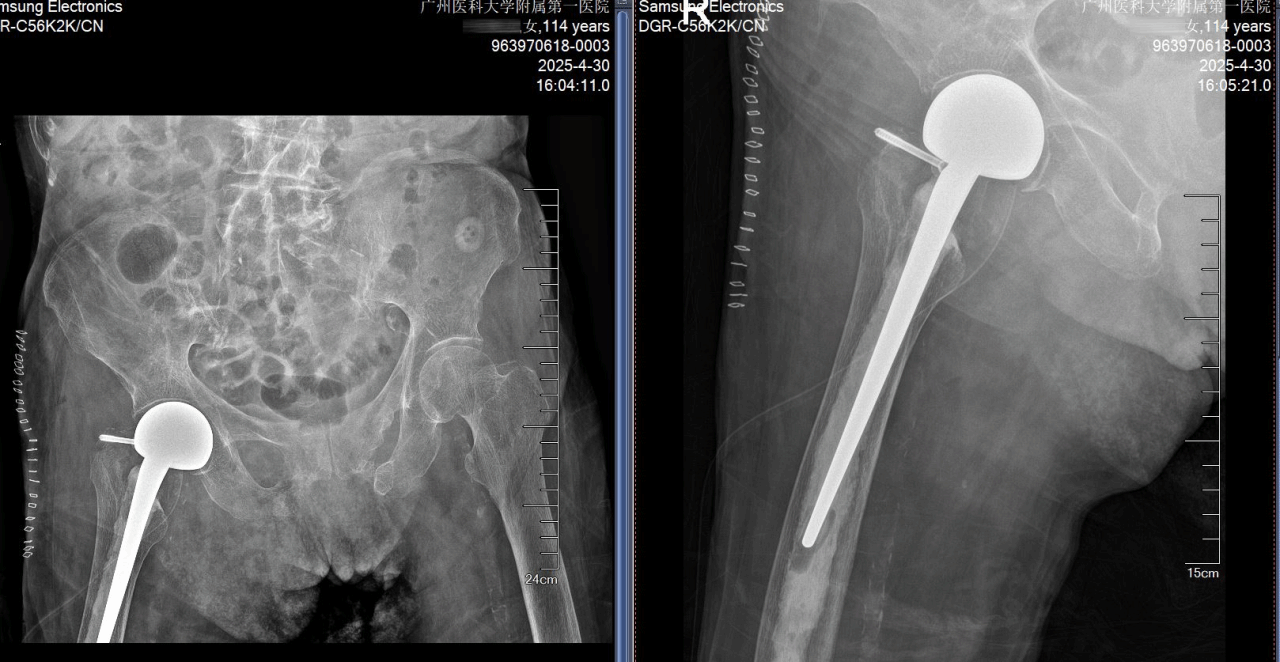

经过精心术前准备,患者各项指标明显改善,考虑到患者骨质疏松非常严重和早期下地活动的要求,经多学科讨论,并且与家属充分沟通和慎重考虑,卢伟杰团队最终决定采用水泥型人工股骨头置换术进行治疗。

手术在卢伟杰主任医师的带领下稳步进行,手术团队配合默契、采用骨水泥固定技术,减少出血量、便于患者早期下地行走,在顺利完成关节置换的同时,极大降低手术创伤对病人的影响。由于准备充分,对患者全身情况干扰较少,手术结束后,患者直接返回普通病房,继续康复治疗。

患者术后72小时即实现行走突破,已能在助行器的帮助下行走活动,生活质量得到了显著改善。“她的毅力,连年轻人都自愧不如。”宋丽娟护士长感慨道。这场与时间的赛跑、与生命的较量,是医疗技术的胜利,也是精细化护理与人文关怀的完美结合。

术前术后X光照片